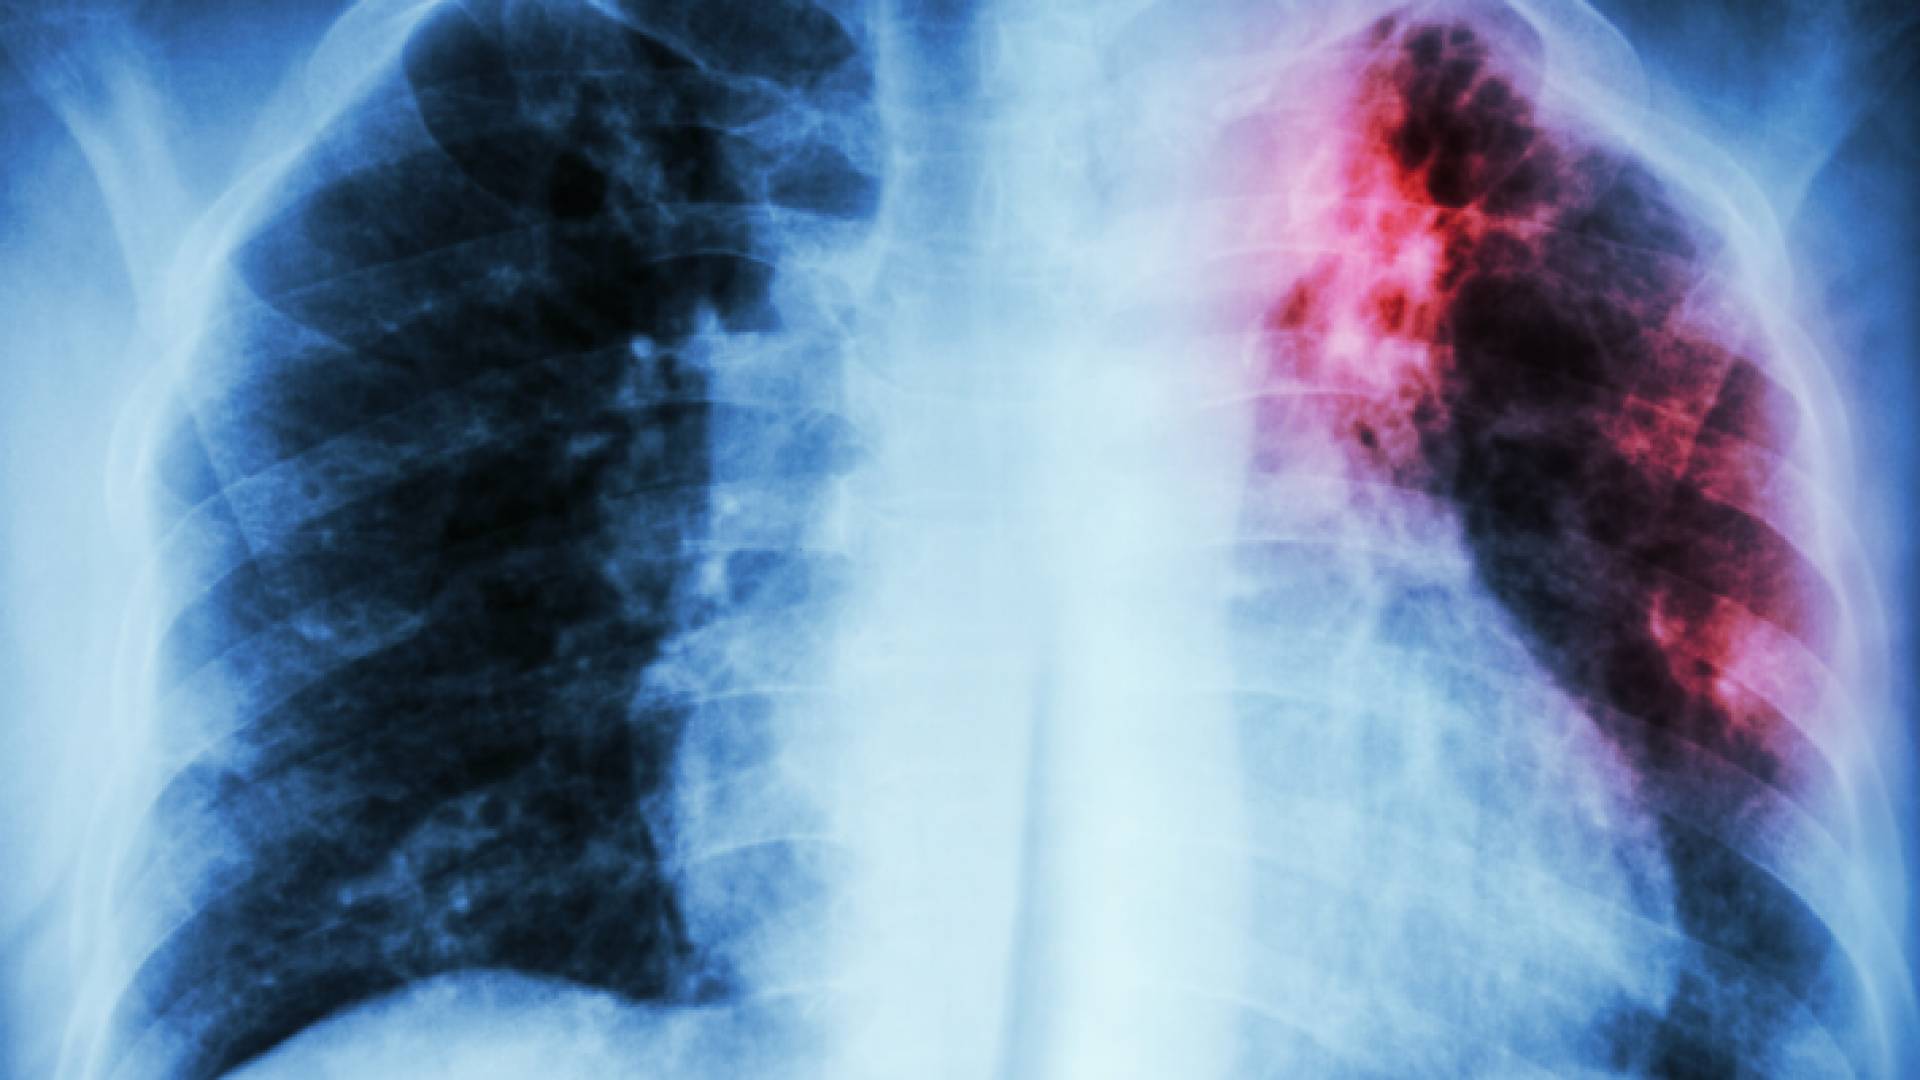

صورة أشعة للرئة